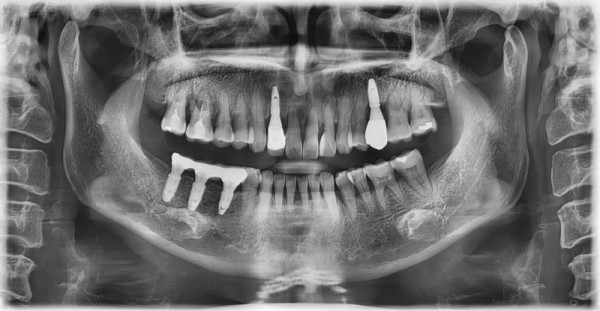

60대 남, 임플란트